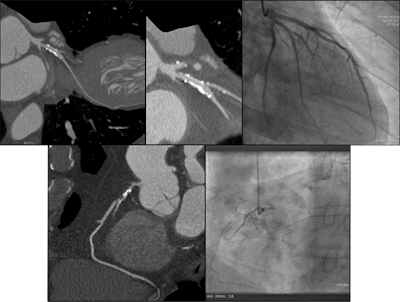

Having conducted an audit of their service for rate and cause of nondiagnosis in 2009, the Plymouth researchers decided to carry out a reaudit. All attendees for coronary CTA (CCTA) examinations for the investigation of coronary artery disease during a three-month period were reviewed. The analysis included 329 patients, and the cohort was similar to the original one, although it was older (59 versus 61 years) and with higher body mass indices.

In the recent audit, CCTA was not attempted in 20 patients. Overall, 13% were not attempted or not diagnostic, compared with 18.2% in 2009. The reasons for nondiagnosis were similar to those before: 57% due to heart rate and rhythm, and 36% unable to breath-hold. The nondiagnostic rate in patients referred by clinicians who had received the team's educational guidelines was 8% compared with 19% in those who had not. The rate for cardiologists was 10.6%, compared with 18.3% for other referrers.